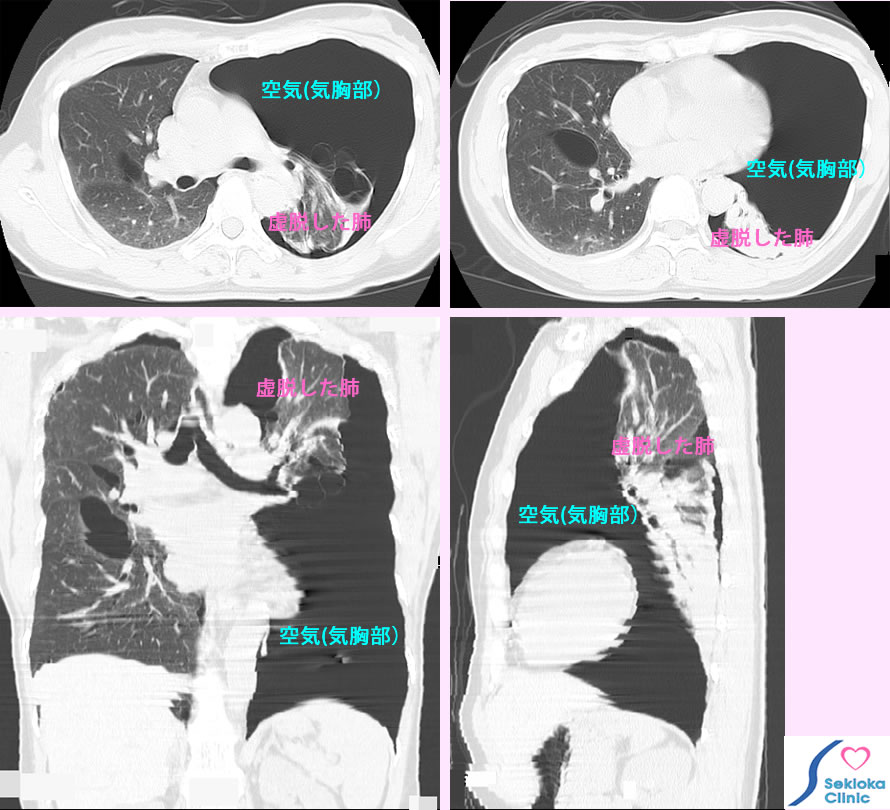

| 診断 | 聴診で呼吸音の低下や胸の打診音の異常で推測され、X線撮影で診断されます。気胸の精査や原因検索にはCTが使われます。参考画像は咳で受診された50歳台の女性で聴診で気胸の疑いがもたれ、MDCTで撮影したものです。MDCTでは任意断面の画像で観察できるので詳細にわかります。 |